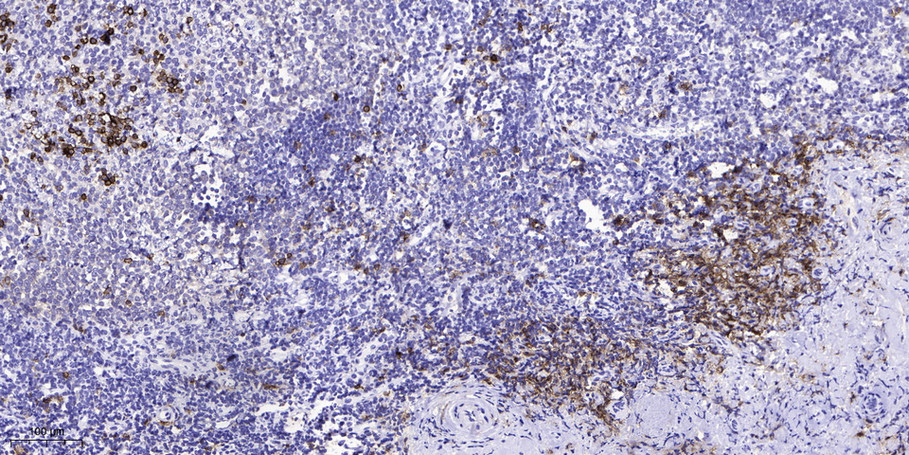

Immunohistochemical analysis of paraffin-embedded human tonsil. 1, Antibody was diluted at 1:200(4° overnight). 2, Tris-EDTA,pH9.0 was used for antigen retrieval. 3,Secondary antibody was diluted at 1:200(room temperature, 45min).